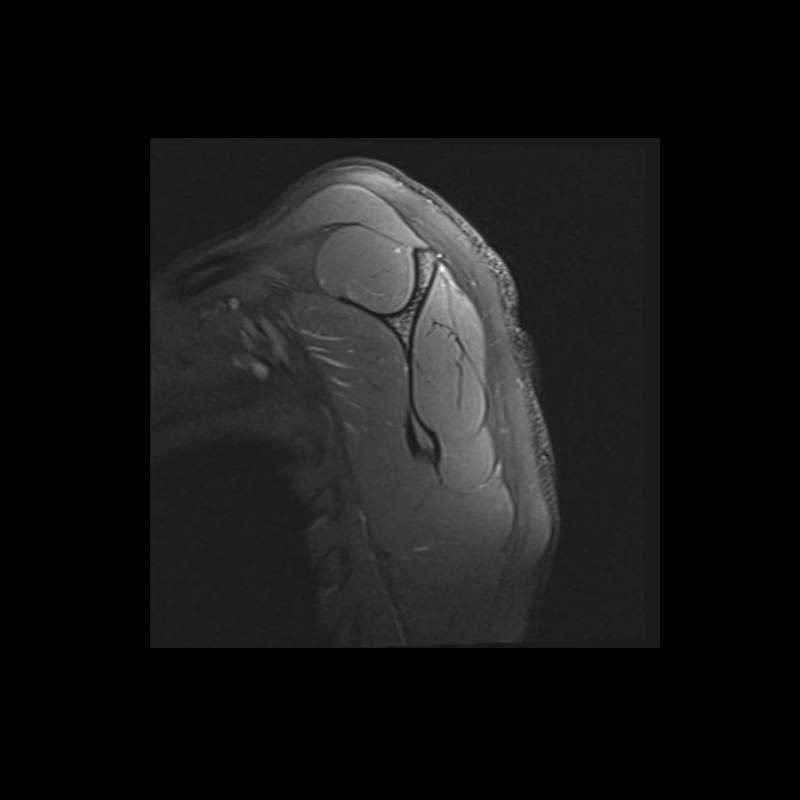

Shoulder MRI Anatomy